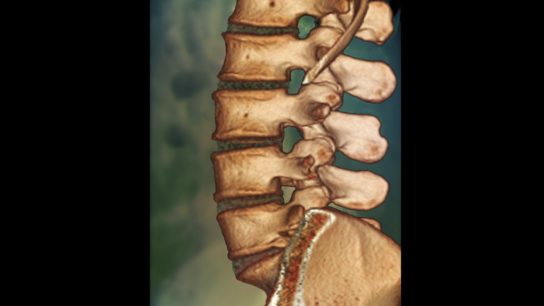

Study authors assessed the impact of splanchnic occlusive disease on spinal cord injury after descending thoracic and thoracoabdominal aneurysm open repair.